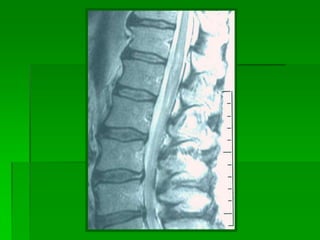

 RM: área ensanchada de hiperseñal (T2)

Diagnóstico  Clínica  RM:área ensanchada de hiperseñal (T2)  Arteriografía? Pocas veces tiene interés práctico